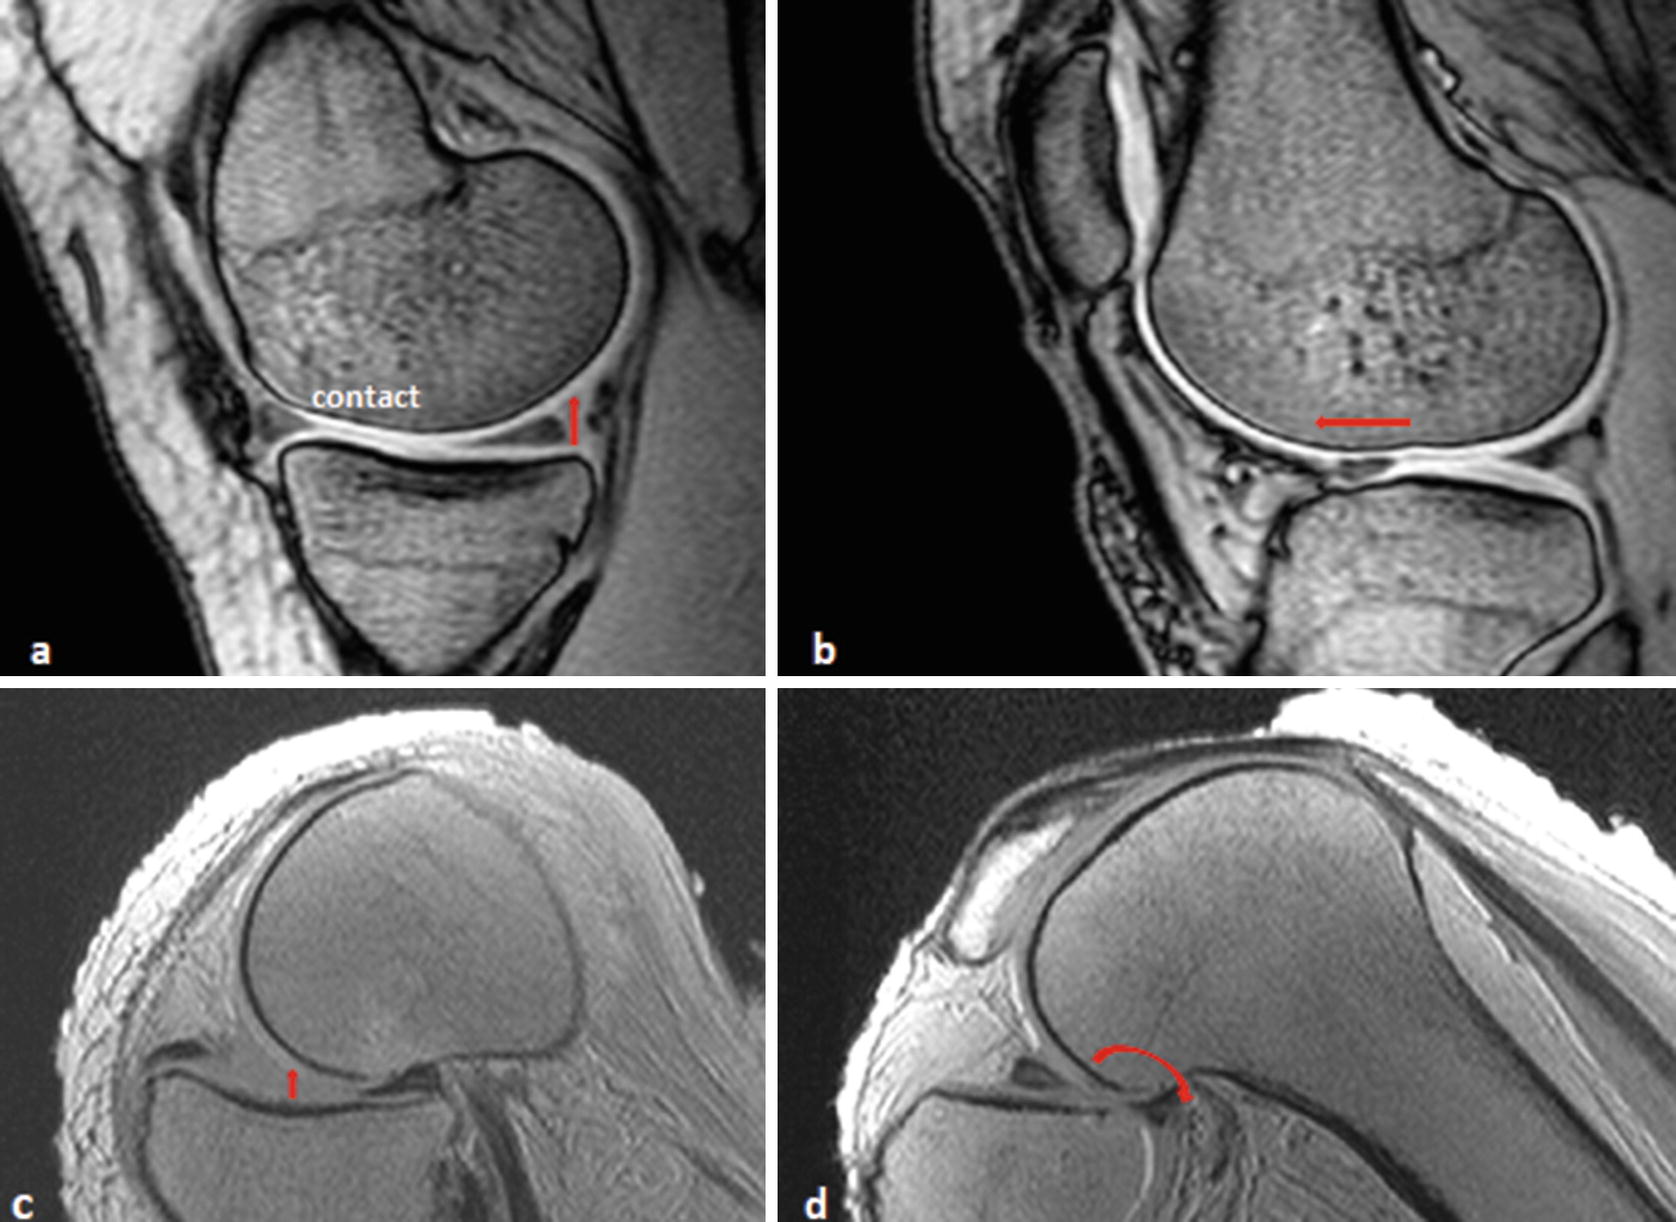

Anterior Knee Pain Missoula Bone Joint from wp02-media.cdn.ihealthspot.com The patellar ligament is the anterior ligament of the knee joint. On the anterior surface of the knee, the patella is held in place by the patellar ligament, which the range of motion of the knee is limited by the anatomy of the bones and ligaments, but allows around. The acl is a band of dense connective tissue which courses from the femur to the tibia.